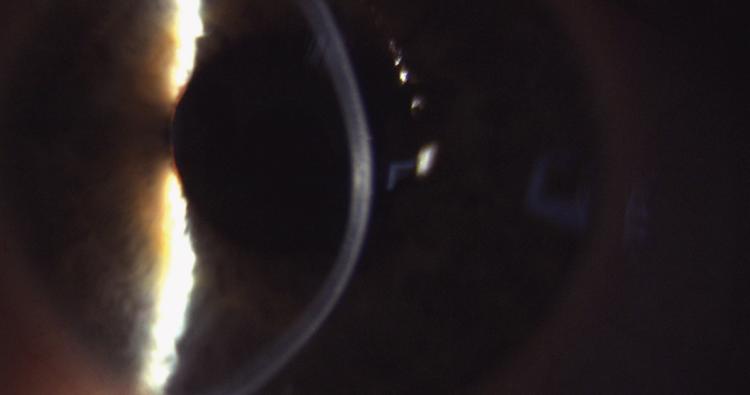

Die ermittelten Werte dienen der Zustandsbeurteilung der KLversorgung und sollen auch Hinweise und Auffälligkeiten aufdecken, die eine Progression des Keratokonus vermuten lassen. Die Beurteilung, ob ein Keratokonus progressiv ist, ist von hoher Bedeutung, da der Patient dann möglicherweise von einer Behandlung mit dem CXL­Verfahren profitieren würde. Eine im  Global Consensus on keratoconus [10] befragte Expertengruppe mit 36 Teilnehmern stellt dazu fest, dass aktuell keine einheitlichen Kriterien und Bewertungsmaßstäbe zur Progressionsanalyse existieren. Die alleinige Messung der Hornhautradien oder Analyse der Hornhauttopographie reicht bei KL tragenden Patienten in der Regel nicht aus, da die Hornhautform nach dem Tragen von KL nicht mit der Form vor der Erstanpassung verglichen werden kann. Durch ungünstige Druckverteilung unter der KL kann es zu einer Epithelverschiebung kommen, die als „corneal warpage“ in der Literatur beschrieben ist. Ob fokale Versteilungen der Hornhautradien dann als Folge einer mechanischen Epithelverschiebung oder als Folge einer Keratokonusprogression auftreten, lässt sich durch eine Kombination aus Topographie und Pachymetrie feststellen. [11] Auch bei durch KL unbelasteten Augen kann die Verdünnung des Hornhautstromas durch eine Zunahme der Epitheldicke kompensiert werden, sodass die Messung der Hornhautradien in diesen Fällen nicht aussagekräftig ist. Abbildung 3 zeigt die spaltlampenmikroskopische Aufnahme einer Hornhaut mit Keratokonus und stromalen Narben. Abbildung 4 zeigt die OCT­Aufnahme derselben Hornhaut wobei die Aufhebung der Strukturen und Schichtgrenzen sowie die Epithelverdickung in Bereichen mit starker stromaler Verdünnung gut zu erkennen sind.

Spaltlampenmikroskopische Aufnahme